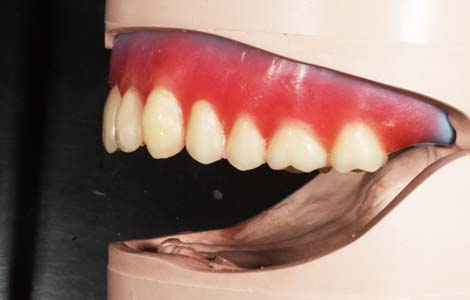

入れ歯の形で違いがわかる

写真の入れ歯の上と下とでは随分形が違いますが、両方とも同じ人の下の入れ歯です。どちらが良いのか、最初は私も全くわかりませんでした。実は多くの歯科医師も、入れ歯の勉強を相当しないと判断ができません。

写真は発音の検査をしているところです。入れ歯の形は、食べ物の流れをコントロールしたり発声時の音を作るのにもとても影響を及ぼします。ですから、一見何の変哲もなさそうなピンクの部分も、より快適な入れ歯を作るためには非常に重要な役割を担っています。こうした細部のこだわりがピッタリの入れ歯作りに必要な作業なのです。